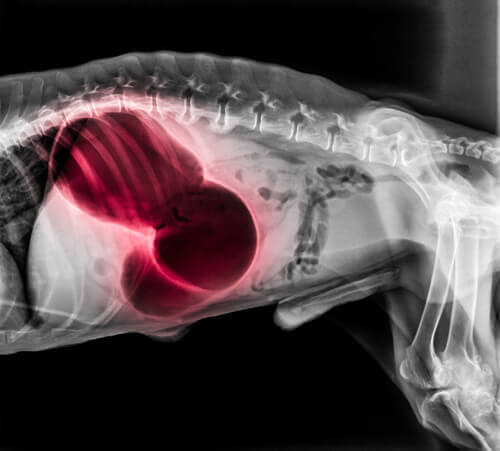

Kalp veya akciğerdeki pıhtılaşma

Kalp veya akciğerlerdeki pıhtılaşma ciddi boyutlarda çeşitli sistematik semptomlar gösterebilir: bayılma, nefes darlığı ve felç gibi. Ayrıca köpeğin diş etleri beyaz veya mavi renkte olabilir ve köpek uyumakta güçlük çekebilir ya da öksürürken kan gelebilir. Akciğer embolisi (pulmoner tromboembolizm) genelde ölümcüldür.